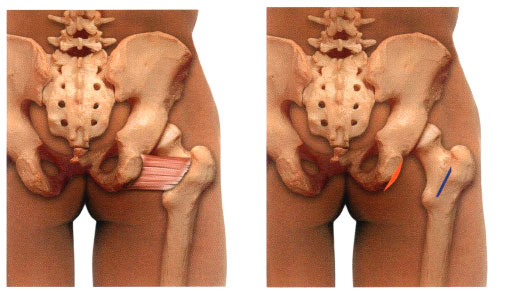

Квадратная мышца бедра

| текущий | 21:05, 26 сентября 2016 |  | 510 × 291 (39 КБ) | Anes (обсуждение | вклад) | Квадратная мышца бедра |